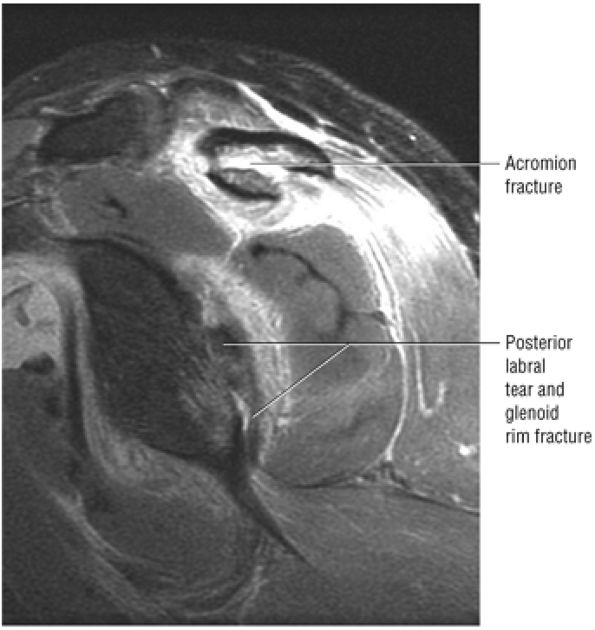

FIGURE 8.102 ● (A) The anterior undersurface of the acromion and the coracoacromial ligament form the coracoacromial arch. The subacromial subdeltoid bursa facilitates the passage of the rotator cuff and proximal humerus under the coracoacromial arch. (B) A superior axial image shows the anterior-to-posterior extent of the coracoacromial (CA) ligament perpendicular to the supraspinatus tendon. The fluid in the subacromial-subdeltoid bursa represents fluid between two serosal surfaces in contact with each other. One serosal surface is contributed by the undersurface of the coracoacromial arch and deltoid, and the other serosal surface is on the bursal side of the cuff.

|

![]() |

FIGURE 8.103 ● Pseudospur. The normal broad attachment of the coracoacromial ligament to the inferior surface of the acromion is shown on (A) T1-weighted coronal oblique and (B) sagittal oblique images. The low-signal-intensity acromial cortex (black arrows) and adjacent coracoacromial ligament and lateral slip of the deltoid attachment (white arrows) give the false impression of a small subacromial spur in the coronal plane. This pseudospur should not be misinterpreted as impingement; otherwise, unnecessary acromioplasties may be performed on patients with a normal coracoacromial ligament attachment and no associated acromial spurs.

-

Impingement syndrome, a clinical diagnosis, is characterized by a range of MR findings from tendinosis to rotator cuff tears.

Intrinsic impingement is associated with shoulder instability.